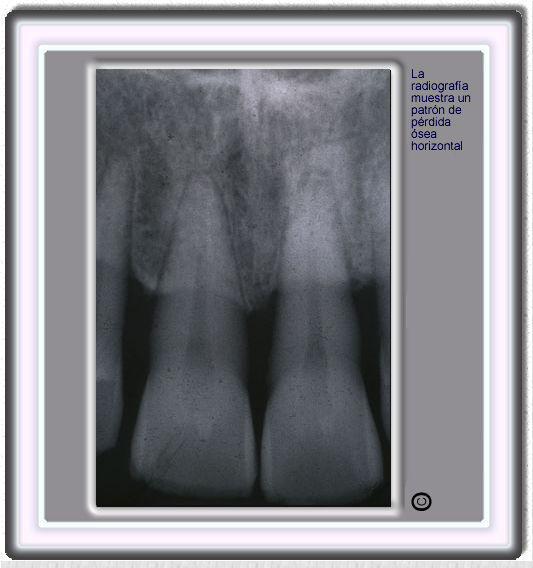

image 578